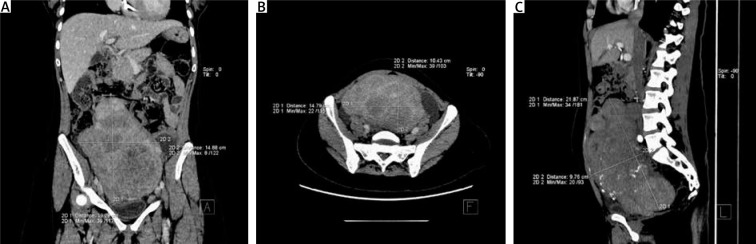

Uterine fibroids are the most common pelvic benign tumours occurring in women of reproductive age. Current treatment options include surgical procedures, pharmacological therapies, and minimally invasive procedures. The most commonly applied and accepted minimally invasive procedure used in the treatment of symptomatic uterine fibroid is uterine artery embolisation (UAE). Uterine artery embolisation is a minimally invasive procedure that can be used either as an auxiliary method or the main treatment method of symptomatic uterine fibroids. We would like to present the application of pre-operative UAE before hysterectomy in anaemic women with giant uterine fibroid (21.9 × 14.9 × 10.4 cm) and HIV-associated nephropathy. Among the possible treatment options for uterine fibroids in cases like the one presented in our manuscript, hysterectomy is the treatment of choice. However, surgical treatment in a patient with severe comorbid conditions and giant uterine fibroid carries serious risk of perioperative complications. Pre-operative UAE decreases such risk by reducing blood loss during hysterectomy and shortening operation/anaesthesia time. Although the benefits of pre-operative UAE before planned myomectomy or hysterectomy in high surgical risk patients with large fibroids has yet to be confirmed in a well-designed clinical trial, this procedure seems to be a promising tool to reduce the risk of perioperative complications in such patients.

Abstract Image